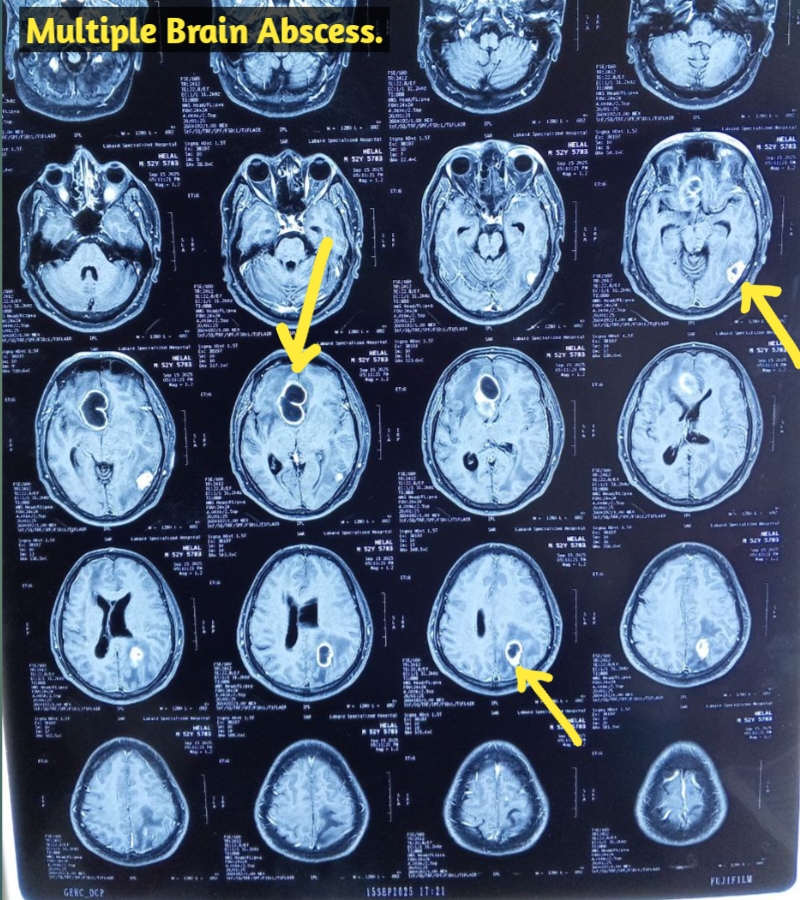

মাথা ব্যথা, ঘাড় ব্যথা, কোমর ব্যথা, পিএলআইডি সমস্যা, হেড ইনজুরি , স্পাইন ইনজুরি , স্পাইনের রড-স্ক্র ফিক্সেশন, মস্তিষ্ক - স্নায়ু - মেরুদণ্ড ব্যথা, স্পাইনাল টিউমার, ব্রেইন টিউমার, প্যারালাইসিস বা পক্ষাঘাত, স্ট্রোক, হাত - পায়ে ব্যথা, হাতে পায়ে ঝিমঝিম ভাব , শিশু নিউরোসার্জারি , ভাসকুলার নিউরোসার্জারি বিশেষজ্ঞ ও নিউরোসার্জন।